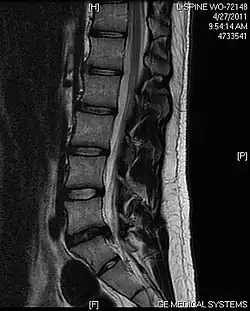

IRM sagittale montrant une hernie discale de niveau L5-S1.